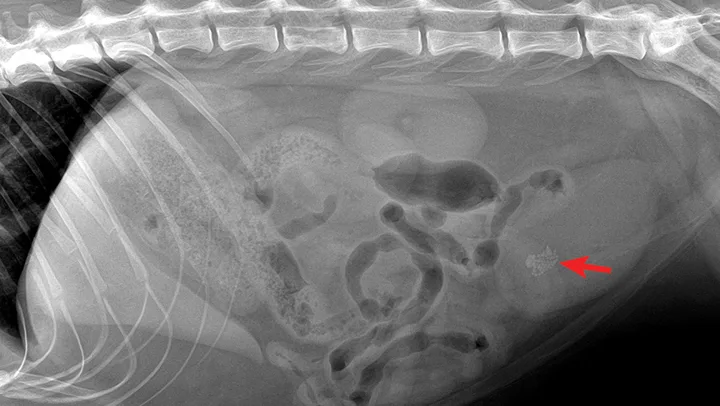

Figure 2

Radiograph showing bladder stones composed of struvite (magnesium ammonium phosphate). Radiograph courtesy of Red Bank Veterinary Hospital, Tinton Falls, New Jersey

Once the obstruction has been cleared, additional diagnostic tests may be performed (eg, urinalysis, urine culture, abdominal radiography and/or ultrasonography) to investigate underlying conditions and identify bladder stones and neoplasms. (See Figure 2.) In patients requiring urinary surgery, the urinary catheter is often left in place until the procedure has been performed.